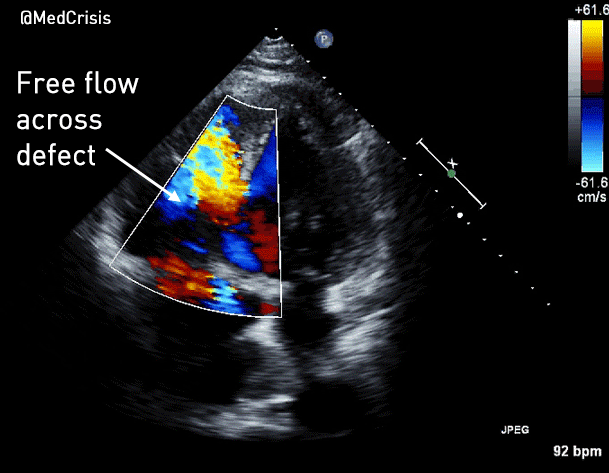

Apical 4 chamber colour Doppler:

There is free flow between LV and RV.